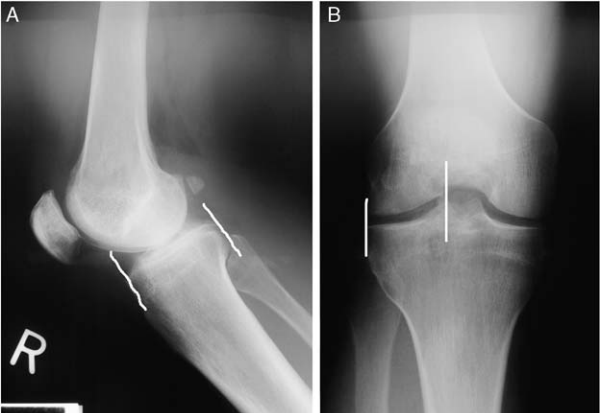

수술을 할때 meniscus의 width, length 측정이 중요합니다. width는 바로 측정을 해보면 되지만 (spine 기준) length의 경우 sagittal 길이의 70%를 LM, 80%를 MM 으로 생각하면 됩니다. hooked depth gauge 를 fine 하게 조정을 잘 하는 과정이 중요합니다.